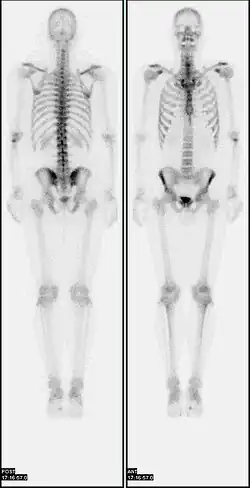

Iodine-123 whole body scan for thyroid cancer evaluation. The study above was performed after the total thyroidectomy and TSH stimulation with thyroid hormone medication withdrawal. The study shows a small residual thyroid tissue in the neck and a mediastinum lesion, consistent with the thyroid cancer metastatic disease. The observable uptakes in the stomach and bladder are normal physiologic findings.